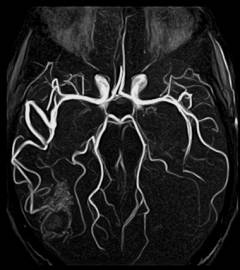

Ангиография головного мозга

Ангиография головного мозга, или церебральная ангиография – метод исследования сосудов головы для выявления патологий мозга.

Где вводят контрастное вещество? Процедура начинается с катетеризации плечевой, локтевой, подключичной или правой бедренной артерии. Катетер продвигается до места разветвления сосудов мозга, где вводится контрастное вещество.

Когда выполняется рентгенография? После первой порции контраста делают рентгеновскую съемку головы в нескольких проекциях (спереди и сбоку). Снимки анализируются сразу. Для исследования более удаленных участков вводится новая порция контраста, и съемка повторяется. Когда контраст проходит через ткани и попадает в вены, выполняется следующая серия снимков. На этом этапе катетер или пункционная игла удаляются, и процедура завершается.

- Неврология – ангиография головного мозга выявляет аневризмы, гематомы, опухоли и места кровотечения при инсульте.

Ангиография головного мозга помогает выявить аневризмы, стенозы и другие аномалии, что критично для предотвращения инсультов. Исследование сосудов нижних конечностей позволяет диагностировать периферическую артериальную болезнь, которая может привести к серьезным осложнениям, включая гангрену. Коронарная ангиография, в свою очередь, является ключевым методом для оценки состояния коронарных артерий, что особенно важно для пациентов с сердечно-сосудистыми заболеваниями. Врачи подчеркивают, что своевременная диагностика с помощью ангиографии может существенно повысить шансы на успешное лечение и улучшение качества жизни пациентов.